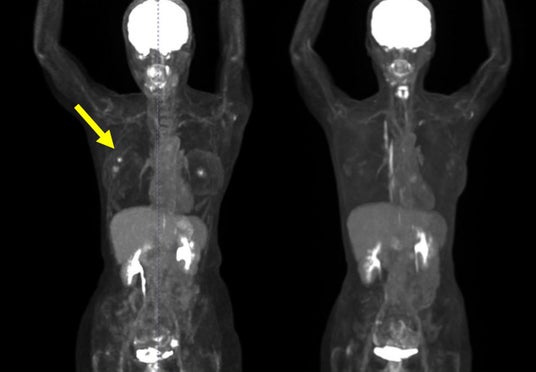

・FDG-PET陽性の浅在性腫瘍に対するBNCT(jRCTs031240204)治療10例目:初発乳がん(未手術)

FDG-PETにおける集積がSUV5からSUV1へ低下。治療1カ月後の時点で触診上腫瘍が確認できなくなり、その後2~4カ月の画像診断においても腫瘍は確認されませんでした。(効果判定はCR)

(PET画像) 左:照射前 右:照射後